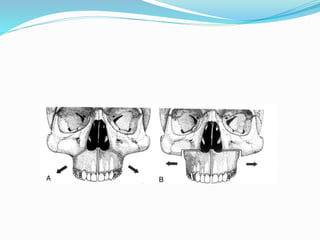

Transverse Maxillary

Distraction Osteogenesis

Incidence and Origins

 Incidence 8 – 18 %

Clinical Evidenses

 Posterior crossbite

 Crowding

 Hourglass arch

 Deep palate

 Dental or skeletal

 Skeletal discerpancy

 Narrow maxilla- normal mandible

 Normal maxilla- wide mandible

 Narrow maxilla- wide mandible

 Transverse deficiency

 Maxillary hypoplasia

 Mandibular prognatism and sagital deficiency

 Apertognathie

 Repaired clefts